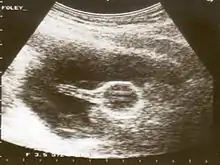

ويمكن أيضا استخدام قسطرة فولي لعلاج ضيق عنق الرحم أثناء تحفيز المخاض. عندما تُستخدم لهذا الغرض، يطلق على هذا الإجراء اسم تسريب المحلول خارج السلوي.[3] في هذا الإجراء، يتم إدخال البالون وراء جدار عنق الرحم ويُنفخ، على سبيل المثال 30 مل في الساعة. يتم سحب الطول المتبقي من القسطرة ليكون مشدود قليلًا. يصنع البالون المنفوخ ضغطًا على عنق الرحم، حيث أن رأس الطفل سوف يسبق الولادة، مما يؤدي إلى تمدده. كما يتمدد عنق الرحم مع مرور الوقت، يتم تعديل القثطار مرة أخرى لتكون مشدودة قليلا، وإعادة ربطها للحفاظ على الضغط على عنق الرحم. عندما يتمدد عنق الرحم بما فيه الكفاية، تسقط القسطرة ببساطة.[4]